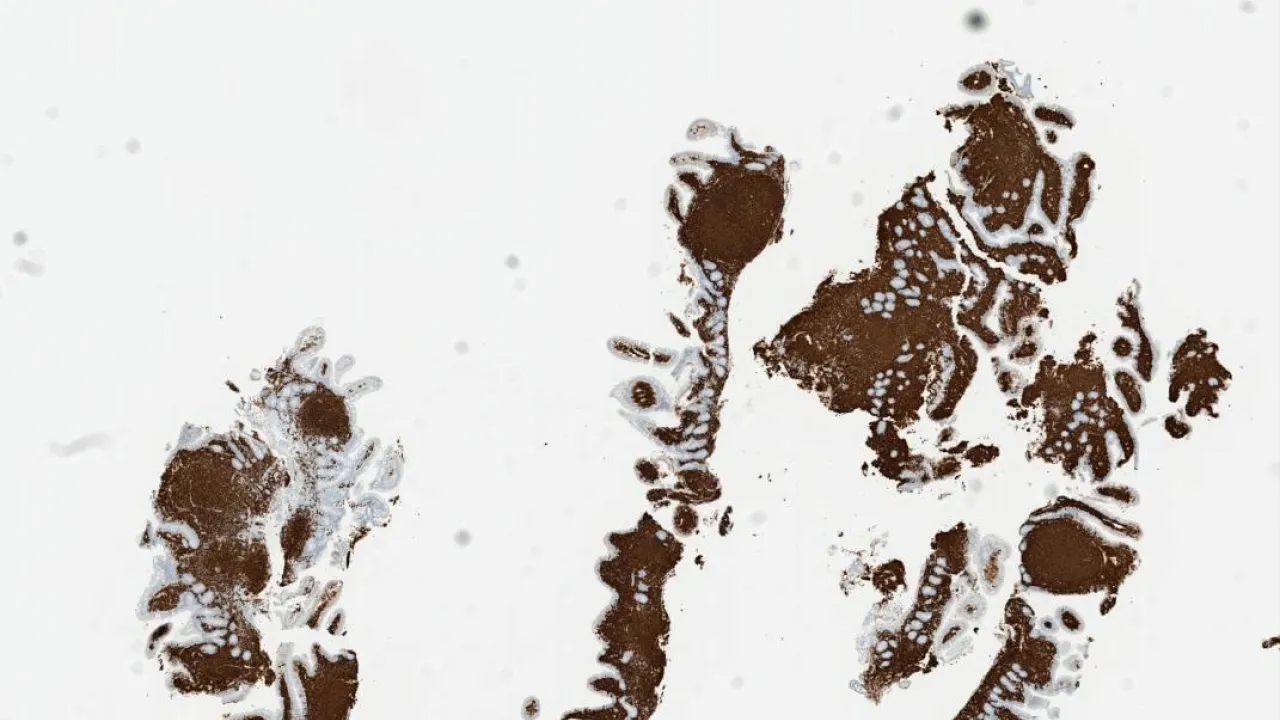

Duodenum, Follicular lymphoma, CD20 stain